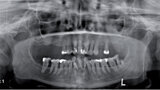

Zubní implantáty – od týmového plánování k esteticky úspěšnému výsledku